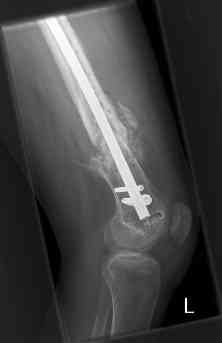

16 yr old boy, high energy motorcycle trauma trauma in July 2005 with:

- distal femoral fracture L

feb 07: retrograde nail + bone graft + BMP

may 07: dynamisation nail

sept 07: locking screw removal (max. dynamisation reached)

nov 07: persistant non-union distal femur; other fractures healed

uneventfully.

All with gradual/partial weightbearing etc. Currently 50-100% weight

bearing, no pain.

Soft tissues are intact. No smoking or diabetes.

CRP <2

What would you do?